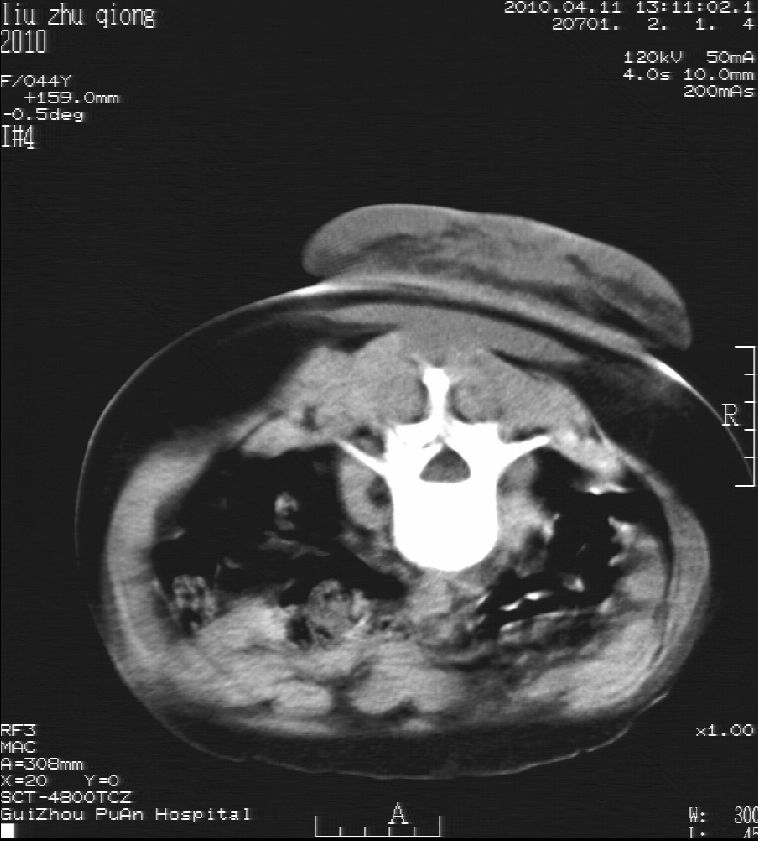

刘某,女,44岁,生第一胎时发现腰背部肿块,黄豆大小,至今17年,呈逐年增大,现行ct检查如下,敬请各位指点。

病史:女,44岁,腰背部肿块,黄豆大小,17年,呈逐年增大。

ct示:骶骨见软组织密度影,似见细条状,或花边状高密度影,考虑不典型钙化灶,向后生长,超出皮肤,可见骶骨破坏,第5幅ct图似与骶管相通。

诊断:脊索瘤

病程长,生长慢,肿块巨大,考虑神经纤维瘤,脂肪密度可以用肿瘤生长过程中包裹入皮下脂肪解释。